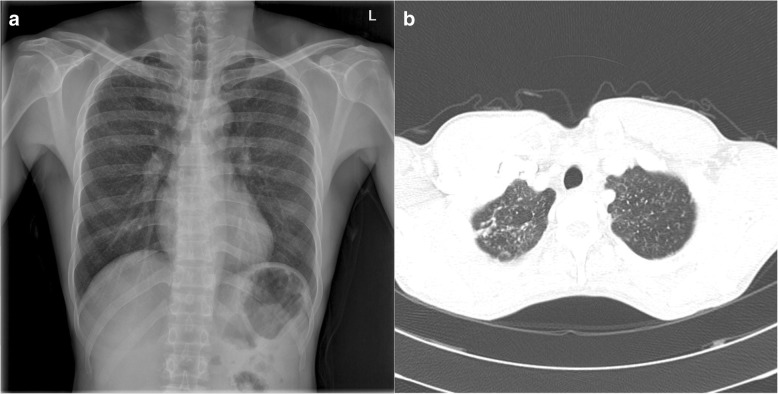

Case Report Pneumoconiosis in a polytetrafluoroethylene (PTFE) spray worker: a case report with an occupational hygiene study